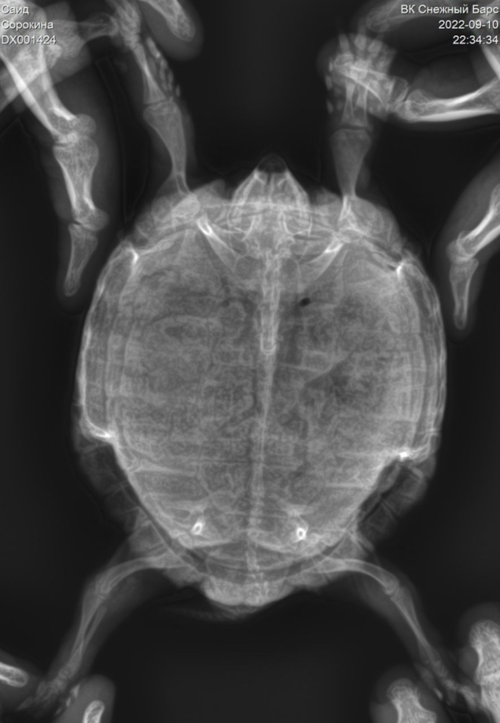

Прикрепила наш более новый рентген и видео на гугл диске с тем как он ползает.

В предыдущем моем посте я паниковала, из-за того, что черепашку с большими отеками предложили усыпить, т.к. лечение было неэффективно. Но оказалось, что мы две недели лечили его не от того, ведь первый врач поставил неверный диагноз. Точнее почечную недостаточность, а в итоге это оказался камень, который не отображается на рентгене, но прекрасно виден на анализах, и все решилось за одну процедуру. Всего-то надо было быть компетентным врачом.

Сейчас меня волнует менее значительная, но все же неприятная его проблема. Черепах перестал использовать задние ноги для передвижения. Они подвижны, он их прячет. Так же второй наш врач (который и спас нам жизнь) сказал что тонус мышц у него нормальный. Но больше ничего конкретного. И эта неопределенность меня и пугает.

Стоит отметить, что перестал использовать задние ноги он именно когда появились отеки, а до этого нормально бегал.